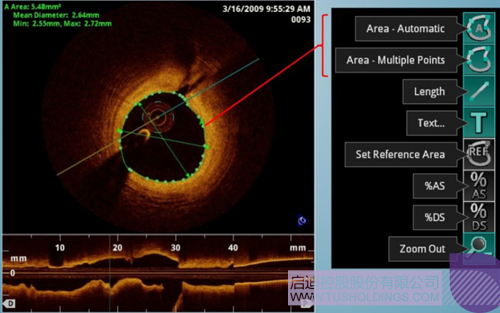

在冠脈介入治療迅猛發展的今天,隨著復雜病變患者日益增多,血管內影像扮演了越來越重要的角色。OCT借助其高分辨率的圖像優勢,可以提供更清晰的病變特征和支架植入情況,OCT存在以下優勢:可更精確的檢測介入治療后的血管內情況,如夾層、支架貼壁不良、組織脫垂等,另外,它在管腔直徑和面積方面的測量精度更高。

血管腔內精準評估